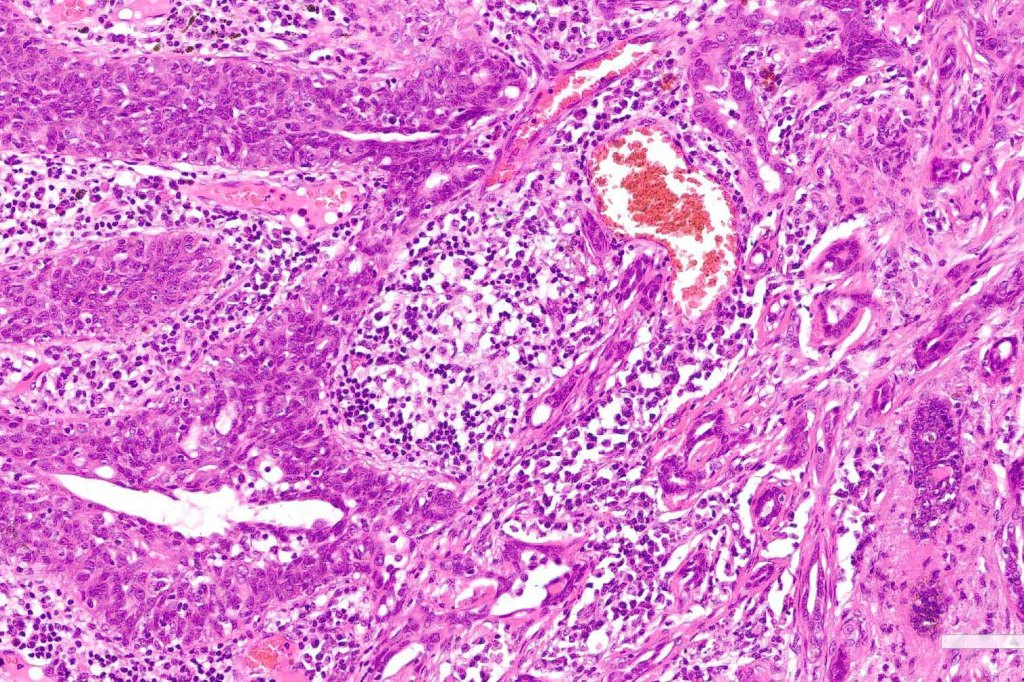

•Widely infiltrating biphasic tumor

•Superficial SCC

•Adenocarcinoma in deeper reaches

•Variable pleomorphism and mitotic activity

•Deep part may show both ducts and glands

•Often extends to the subcutaneous fat

•Perineural infiltration is commonly seen